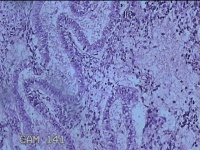

子宫腔内容物

性别

女

年龄

33岁

临床诊断

子宫内膜息肉?子宫异常出血

一般病史

阴道流血12天。

标本名称

大体所见

;纱布一块,内有灰白暗红色不规则碎组织3.5x2.8x1.3cm一堆。

图3